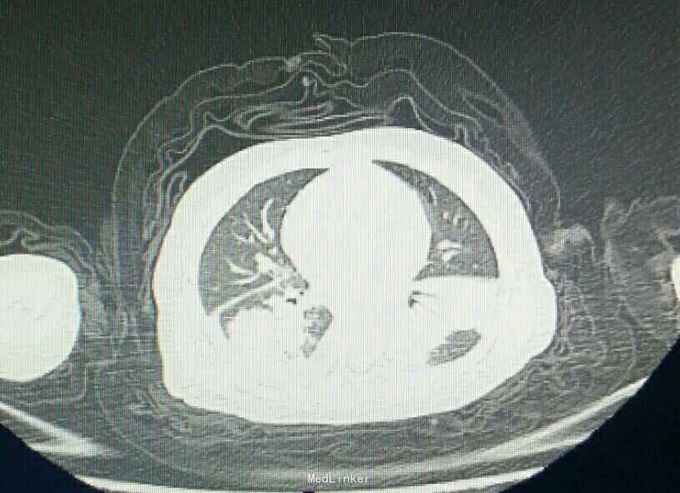

大叶性肺炎一例

患儿,男,4岁,咳嗽三天,不爱活动1天。

胸片,CT.如图,最后一图为一周后复查胸片。